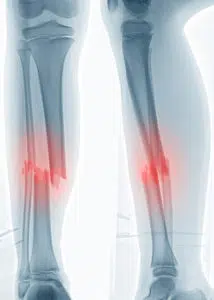

BILAN IMAGERIE

Le bilan d’imagerie consiste à réaliser un bilan radiographique de face et de profil en incluant l’articulation du genou et de la cheville.

Ces radiographies sont réalisées après la réduction du foyer de fracture si l’ouverture de la peau est probable.

Les radiographies permettent d’étudier le type de fracture, la morphologie des traits de fracture, la stabilité de la fracture et les déplacements éventuels.

La fracture d’un os isolé de la jambe est rare et il faudra toujours compléter par des radiographies des régions sus et sous jacentes et explorer en fonction du contexte traumatique rencontré.